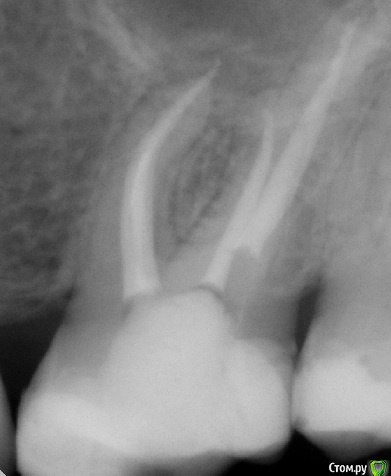

tatsiana.ma Опубликовано 12 мая, 2017 Поделиться Опубликовано 12 мая, 2017 (изменено) Добрый день!Имеются зубы 14 - 26 - (27, 28 удалены более полугода назад, это единственный депульпированный зуб на той стороне) Лечены около полутора года назад с разницей в пару месяцев: 14 - пульпит, в 26 - перидонтит. Сразу после лечения 14 зуб отзывался резкой болью при жевательной нагрузке и при прикосновении к нему, но врач настаивал, что это лишь постпломбировочные боли, но боль не проходила и не уменьшалась в течении нескольких месяцев, после чего врач просто занизил пломбу и фактически вывел зуб из прикуса. После таких манипуляций боль уменьшилась.По факту, оба этих зуба, если надавить пальцем на внешнюю стенку, тихонько и противно ноют, по минуты 3-4-5, потом вроде и спокойно. На прицельных снимках виден вывод пломбировочного материала за апекс. После пломбировки появилась небольшая припухлость щеки и справа и слева, в проекции верхушек корней этих зубов. Смущает, что из всех депульпированных зубов я чувствую только эти два 14 и 26, остальные зубы стоят себе спокойно. Также эти два зуба лечены с применением силера adseal, в других AHplus. Возможно ли, что такие ноющие боли и отечность как реакция раздражения на выведенный за апекс материал и/или проявление аллергической реакции? Имеет ли смысл перепломбировать эти зубы с применением AHplus? p/s/ Сдавала кровь на общий igE - в норме, аллергию непосредственно на пломбировочные материалы у нас не делают. Изменено 12 мая, 2017 пользователем tatsiana.ma Ссылка на комментарий

tatsiana.ma Опубликовано 12 мая, 2017 Автор Поделиться Опубликовано 12 мая, 2017 Желательно сделать томограмму и поискать непройденные каналы КТ перед лечением делала, все каналы найдены:в 14 два канала - первичное эндо,в 26 четыре канала - рэндо, периодонтит (был пропущен 4-й), на контрольном кт гранулёма ушла.Но вот эти странные ощущения и ноющие боли при нажатии... с момента лечения и на протяжении полутора лет сохраняются. С февраля по май этого года выполнено рэндо других четырёх зубов - все ок, никаких посторонних ощущений (делал другой врач). Ссылка на комментарий

tatsiana.ma Опубликовано 13 мая, 2017 Автор Поделиться Опубликовано 13 мая, 2017 (изменено) Еще один вопрос: стекловолоконный штифт из каналов нормально достается? в шестерке в небном корне установлен, на 1/2 длины канала . Прочитала в нете, что свш - это ппц как хреново выпиливаются из канала, особенно когда установлен глубоко. Изменено 13 мая, 2017 пользователем tatsiana.ma Ссылка на комментарий